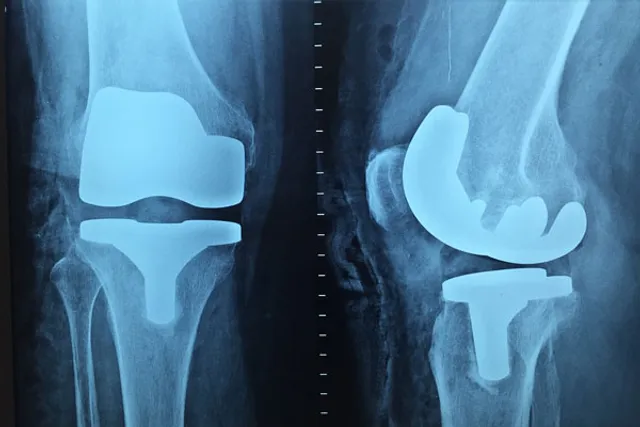

"As age advances, the bones become brittle as calcium reduces in the body leading to bone deformities, stress fractures and affecting the day-to-day life of women. It can be taken care of with extra supplementation apart from a nutritional and dietary intake of calcium available in our daily sources of vegetables and non-veg foods," said Dr. Komal Chavan, who coordinated the mega-camps.